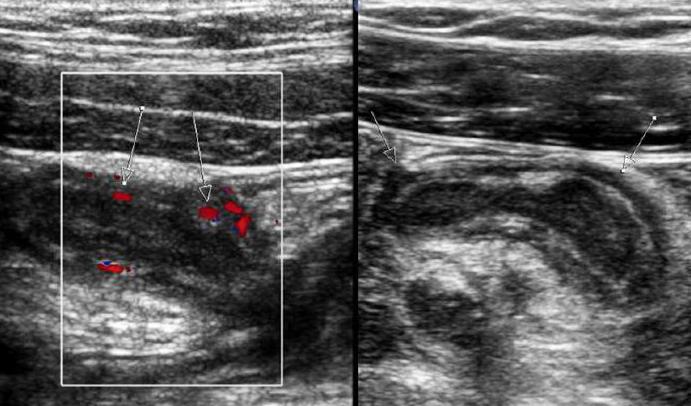

- Ультразвуковое исследование (УЗИ). Этот метод дает возможность определить наличие или отсутствие острого воспаления с точностью 95%.

Точно выявить болезнь помогают инструментальные диагностические процедуры. К самым распространенным относят общие анализы крови и мочи, УЗИ, но в сложных случаях может понадобиться компьютерная томография – она более информативна.